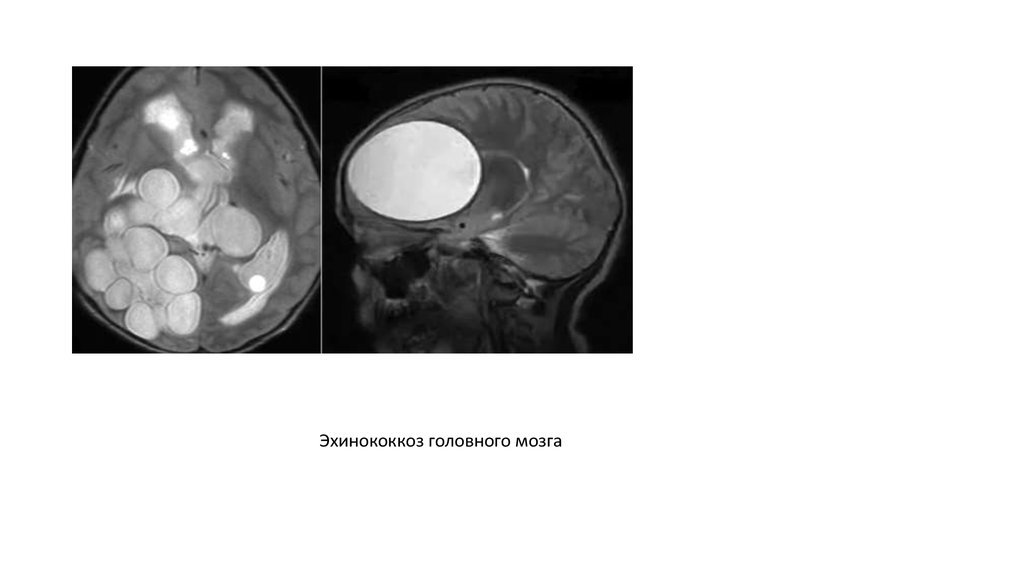

Эхинококкоз головного мозга